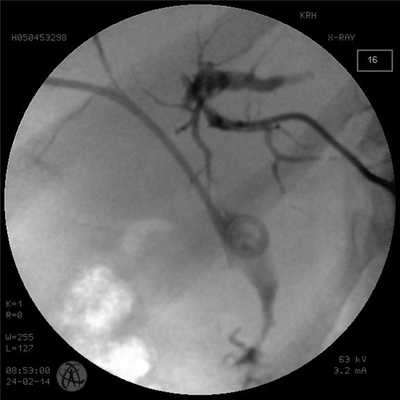

Кроме того, при выявлении признаков нерезектабельности воротной холангиокарциномы дополнительное дренирование желчного дерева контралатеральной половины печени становится целесообразным, поскольку эффективность паллиативной терапии будет зависеть от объема паренхимы печени с восстановленной гемо- и желчединамикой (рис. 2).

Рис. 2. Антеградная холангиограмма пациента с опухолью Клацкина тип II по Bismuth. Супрапапиллярное наружновнутреннее дренирование справа, наружное дренирование слева.